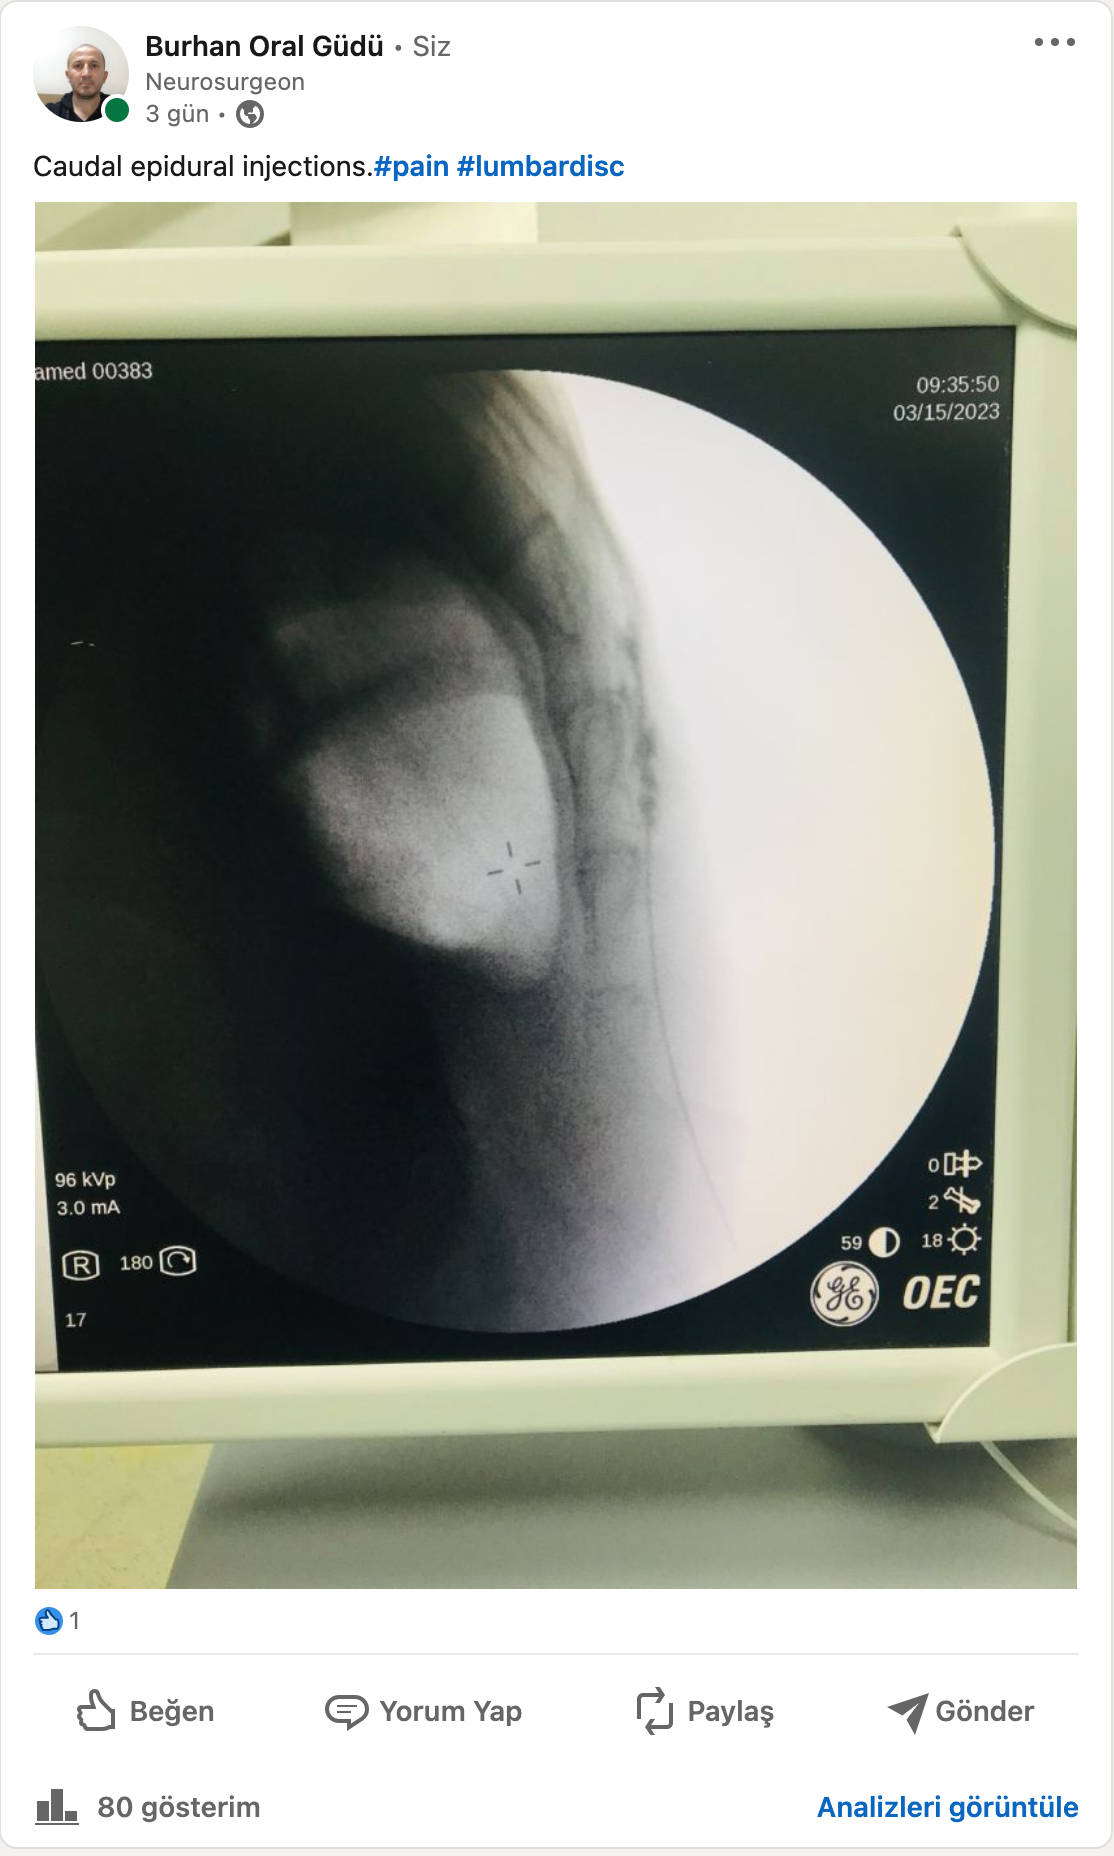

Ağrı İğne Yöntemlerim